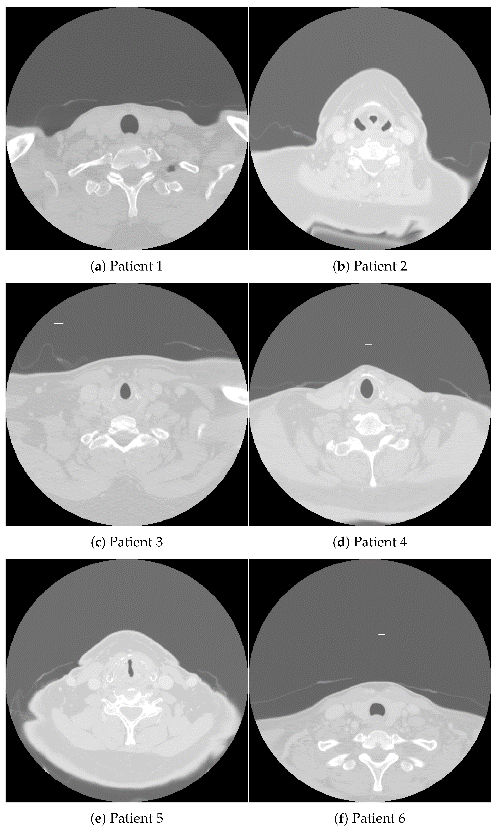

图1.用于支持AI诊断研究的公开数据库图像示例:(A)口咽癌患者上胸部及下颈部横断面 CT 图像;(B)口腔鳞状细胞癌及白斑病的组织病理学图像。